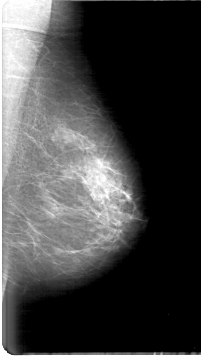

D_4064_1.LEFT_MLO

LEFT_MLO LINES 5386 PIXELS_PER_LINE 3001 BITS_PER_PIXEL 12 RESOLUTION 43.5 NON_OVERLAY